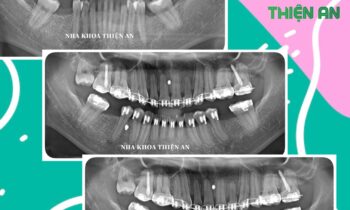

MÀNG PRF KẾT HỢP IMPLANT TẠI NHA KHOA THIỆN AN

Tiếp tục cấy ghép thêm 1 trụ implant cho chị D sau khi chị trải nghiệm cắm 2 trụ implant tại nha khoa Thiện An BMT – Đăk Lăk nhẹ nhàng, êm ái, với công nghệ Màng PRF được chiết lọc từ chính máu tự thân của chính bệnh nhân để tạo ra các tế…